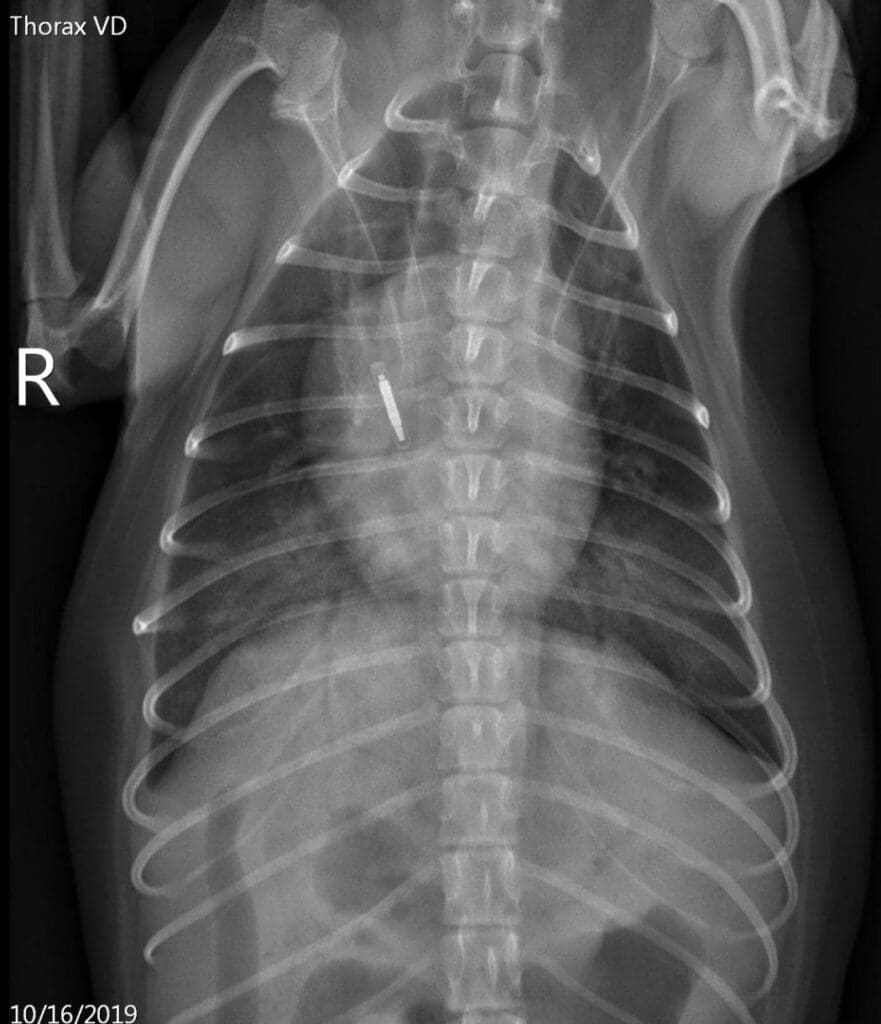

VD view of the thorax 4 hours after the blood transfusion

Our patient had acutely-developed bilateral infiltrates, received a blood transfusion within 6 hours prior to the onset of clinical signs and was likely severely hypoxemic. No heart murmur or left atrial enlargement was evident on physical examination and thoracic imaging, therefore a cardiogenic origin of pulmonary infiltrates is deemed unlikely.